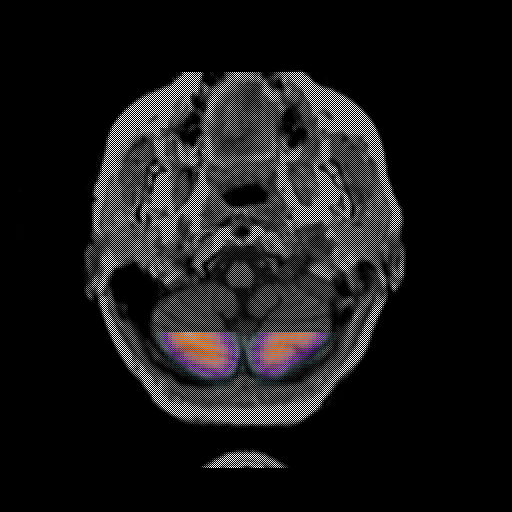

overlay: Slice 6

Slice 6

MRCBFCBF with

T1PDT2T1PDT2